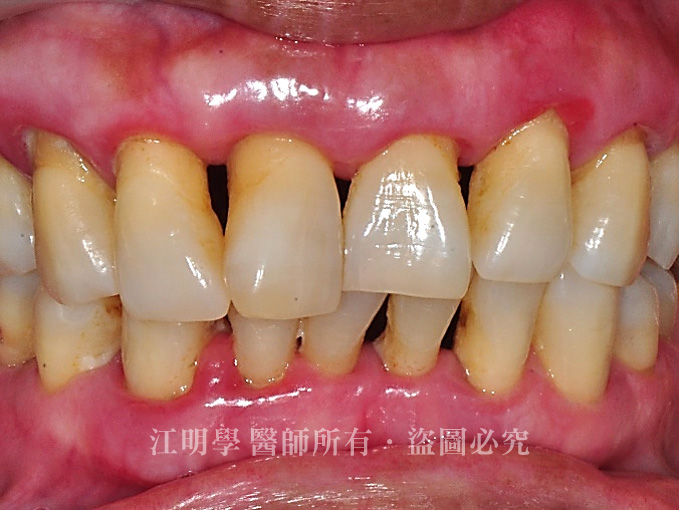

治療前

治療前:後牙多處缺牙導致咀嚼困難

治療前:開口笑時隱約會看到缺牙